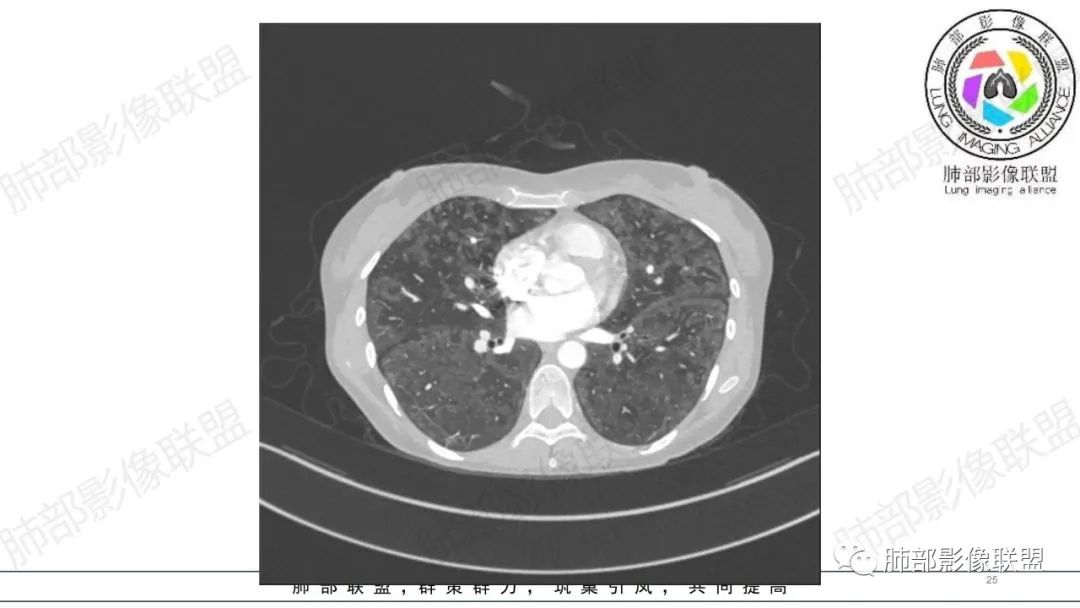

影像资料

34岁女性患者,“哮喘”病史30年,近期有可疑刺激性气体吸入史;因乏力半年,咳嗽、憋气、发热4天就诊;6.1CT提示双肺广泛毛玻璃影及粟粒样结节,胸膜下闲置及血管周闲置,可见树丫征,部分小叶间隔增厚。考虑:1.过敏性肺泡炎,有可疑刺激气体接触史,胸膜下闲置,广泛毛玻璃影,地图样分布,粟粒结节边界模糊,支持过敏性肺泡炎,但糖皮激素治疗效果不佳,且动态复查血常规血红蛋白进行性降低,过敏性肺泡炎 不符合;2.肺含铁血黄素沉积症:患者30“哮喘”病史,可能为肺含铁症状,肺部CT提示双肺弥漫毛玻璃影及粟粒结节影,中下肺明显,肺底部分小叶间隔增厚,近期咳嗽、憋气、发热,血常规血红蛋白进行性下降,考虑肺含铁急性期症状,但临床无咯血症状,肺含铁不典型。综合考虑:肺含铁血黄素沉积症>过敏性肺泡炎。

年轻女性 ,急性喘息发热,肺部影像弥漫磨玻璃密度,部分细小腺泡结节,胸膜下黑线显示,短期复查,病变密度增高,下肺明显,血管周围肺组织累及较少、且逐渐成小叶间隔分布。考虑弥漫肺泡内病变,并经淋巴道转移,下肺比上肺明显,多为免疫细胞功能下肺较强。1.过敏性肺泡炎,有相关病史,三层密度特点、头尾测分布,符合。2 肺泡微石症,多有钙化,且缓慢起病,病程不太符合,放待排。3 吸入相关肺损伤,有病史,疾病演变过程也符合渗出-肉芽肿改变,建议详细询问病史。4 感染性病变,结核?病变气道分布为主,如此弥漫且没有树丫不符合。5.巨细胞病毒,可以磨玻璃 结节 改变,没有免疫缺陷病史。最后考虑吸入所致 1过敏性肺泡炎、吸入性肺损伤 鉴别肺泡微石症。

血管内大B

同意血管大B

肺内气腔磨玻璃结节,肝脾肿大,治疗后间质改变,弥漫大B可能